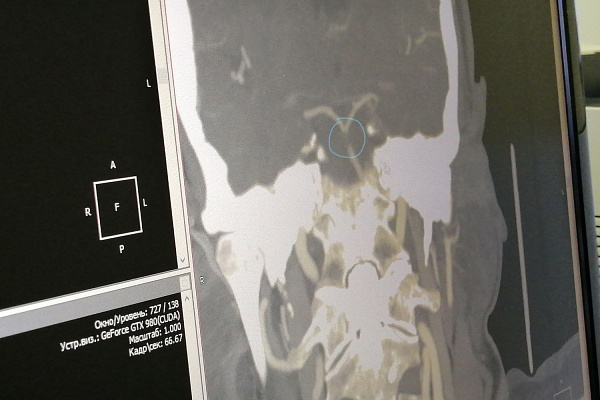

В травмбольницу пациентку доставили уже в коме. Базилярная артерия – единственный сосуд, снабжающий кровью, а значит и кислородом, ствол головного мозга. Сантиметровый тромб закупорил её полностью, перекрыв кровоток.

Пациентку сразу подали в рентгенохирургическую операционную, где на современном ангиографе ей выполнили тромбоэкстракцию. К вечеру того же дня она уже была в сознании, без нарушений речи и двигательных функций. На данный момент женщина проходит курс реабилитационных мероприятий.